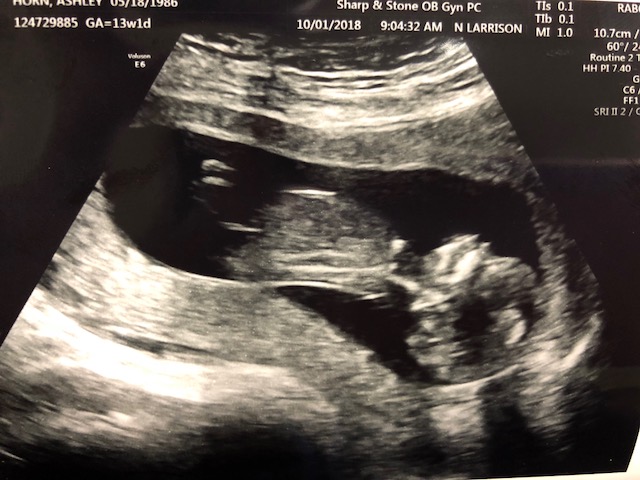

I didn't ask for a nub shot but is the nub visible in this pic? If so, do you think its a boy or a girl nub? Baby is 12 weeks and 1 day.

I went and got another ultrasound I don't think the baby was cooperating lol. Here are two of the best pics which i think may have a nub. What do you ladies think? I would love any guesses.Attachment 40481Attachment 40482